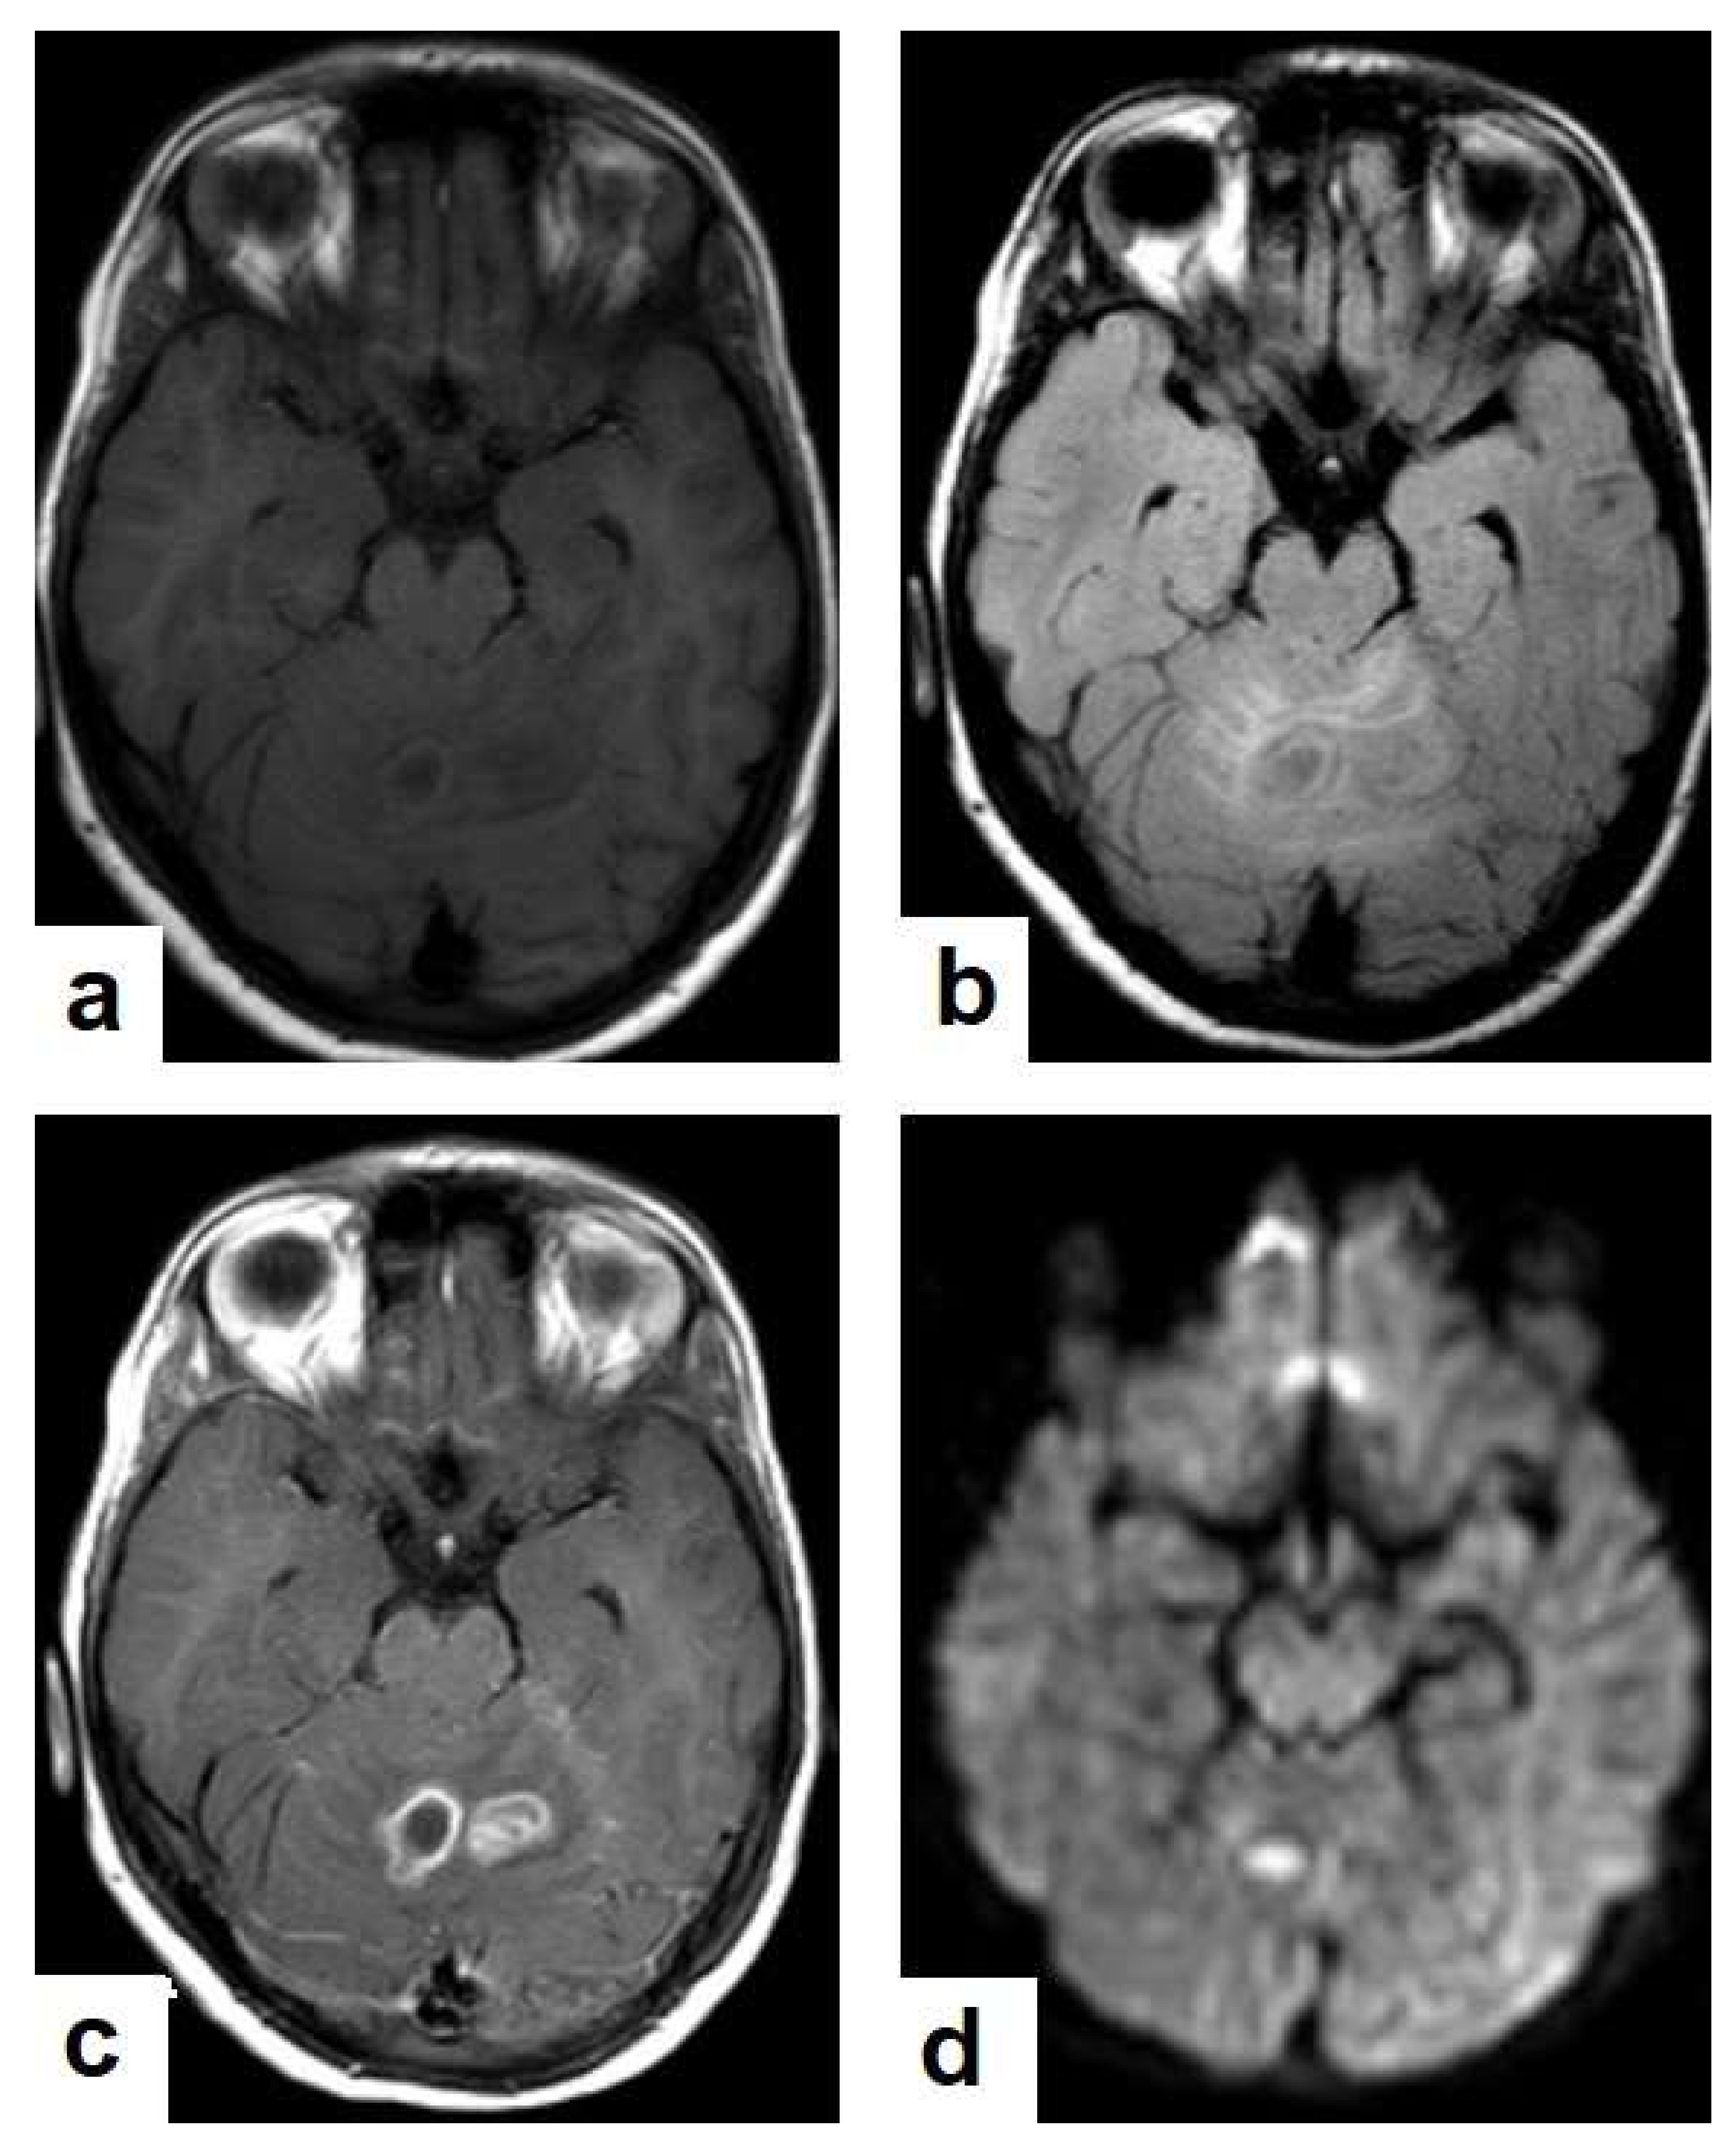

• Tuberculous abscesses (Figure 15, Figure 16 and Figure 17) are an infrequent pattern of brain TB, which are present in immunocompromised and elderly patients. They occur either due to the progression of cerebritis or the liquefaction of tuberculoma. On a brain CT, it occurs as a low density area with ring enhancement after contrast administration and the surrounding low density area of edema. On a brain MRI, it appears as a circular or elliptical area of low intensity with ring enhancement after contrast administration and surrounding low intensity area of edema on T1WIs and high intensity area with a high intensity surrounding edema. Tuberculous abscess is a difficult differential diagnosis of a pyogenic abscess, pilocystic astrocytoma, and other cystic lesions. MR spectroscopy may help in differentiating tuberculous from a pyogenic abscess [27,33].

Figure 17. A tuberculous abscess in the cerebellum of a 13-year-old female (same patient as Figure 16). Selected images of brain MRI (a) T1-weighted image (WI), (b) FLAIR-WIs, (c) T1-WI with contrast, and (d) diffusion-weighted (DW) image. The images show a well-defined lesion in the cerebellum with low signal intensity content and a high signal intensity capsule on T1WI and FLAIR (b), marginal enhancement on T1WI with contrast administration (c), and restricted diffusion on DWI (d).